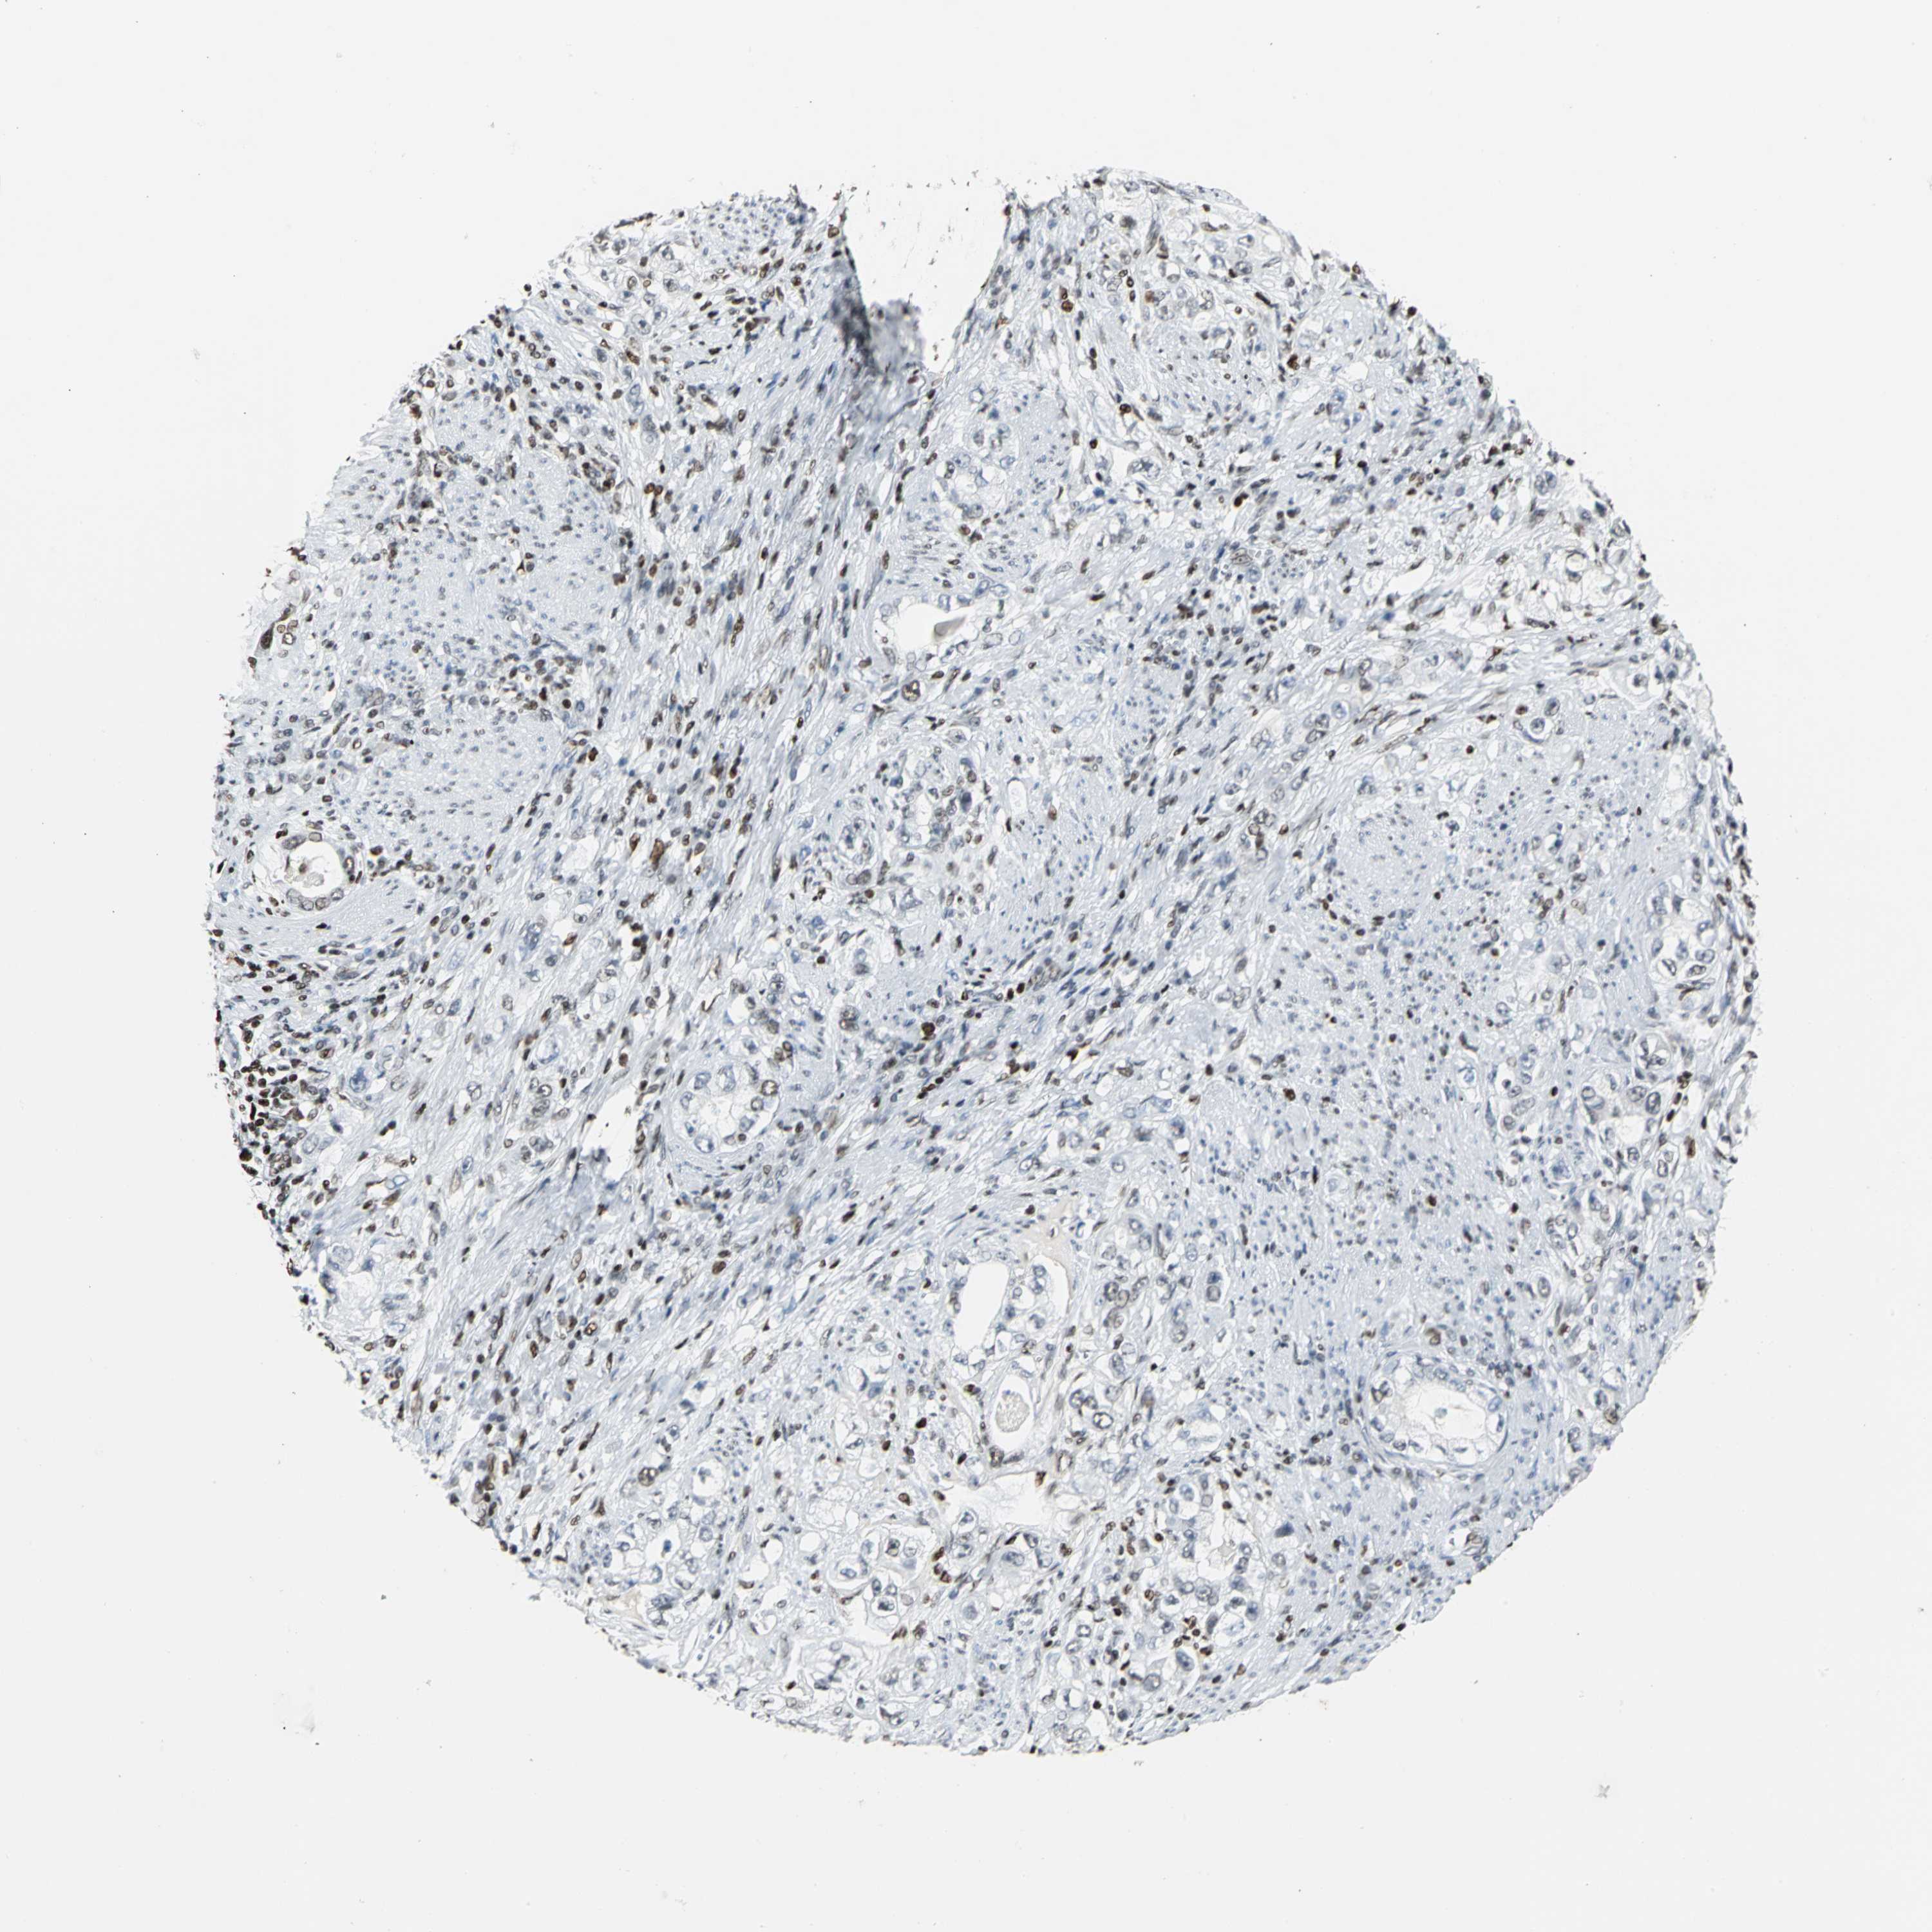

STOMACH CANCER - Protein expressioni

A mouse-over function shows sample information and annotation data. Click on an image to view it in a full screen mode. Samples can be filtered based on level of antibody staining by selecting one or several of the following categories: high, medium, low and not detected. The assay and annotation is described here.

Note that samples used for immunohistochemistry by the Human Protein Atlas do not correspond to samples in the TCGA dataset.

Antibody stainingi

Antibody staining in the annotated cell types in the current human tissue is reported as not detected, low, medium, or high, based on conventional immunohistochemistry profiling in selected tissues. This score is based on the combination of the staining intensity and fraction of stained cells.

Each image is clickable and will lead to virtual microscopy that enables deeper exploration of all samples and also displays staining intensity scores, fraction scores and subcellular localization as well as patient and tissue information for each sample.

Antibody HPA004911

Staining

High

Medium

Low

Not detected

Intensity

Strong

Moderate

Weak

Negative

Quantity

>75%

75%-25%

<25%

None

Location

Nuclear

Cytoplasmic/membranous

Cytoplasmic/membranous,nuclear

Adenocarcinoma, NOS

Adenocarcinoma, High grade